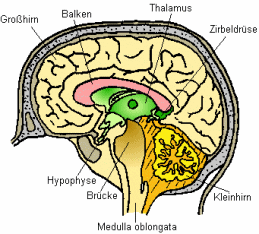

Schema des

Gehirns mit Beschriftung. Auch das Gehirn ist

Quecksilberwirkungen ausgesetzt, wenn

Quecksilberdampf eingeatmet wird.

Insbesondere der auf diese Weise erfolgende Übergang von

Hg-Dampf durch die Blut-Hirn-Schranke ins Gehirn (hierzu

Hursh et al. 1988) ist von toxikologischer Relevanz. Die

als Hg-Dampf wegen dessen Lipoidlöslichkeit

(Fettlöslichkeit) ins Gehirn gelangten Hg-Mengen (S.9)

können nach der Oxidation dort als Quecksilber-Ionen das

Gehirn kaum mehr verlassen. Es kommt zu Anreicherungen von

Quecksilber im Gehirn (Friberg / Mottet 1989; Kuschinsky /

Lüllmann 1989 S.531). Die Halbwertszeit von Quecksilber im

Gehirn

- also diejenige Zeitdauer, die vergeht, bis sich die

Konzentration im angegebenen Organ bzw. im Blut auf 50 %

der Ausgangskonzentration reduziert hat,

d.h., dass etwa sechs Halbwertszeiten verstreichen müssen,

bis die betreffende Substanz den Körper bzw. das Organ

weitgehend verlassen hat -

beträgt bis zu 18 Jahre (Ohnesorge 1982, abgedr. auch

1992; Sugita 1978).

Das Gehirn als eines der Zielorgane des Speichergifts

Quecksilber ist bei einer längerfristigen

Hg-Dampf-Exposition also besonders gefährdet. Durch die

spezifische Anreicherung von Quecksilber in den

Hirnarealen lassen sich die Schädigungen des zentralen

Nervensystems und die zentralnervösen Symptome erklären,

die das Krankheitsbild einer chronischen

Hg-Dampf-Vergiftung mit prägen. Angesichts der extrem

langen Halbwertszeit des ins Gehirn gelangten Quecksilbers

ist auch die Fortdauer der Symptomatik selbst nach

Beendigung der Exposition wissenschaftlich erklärbar.